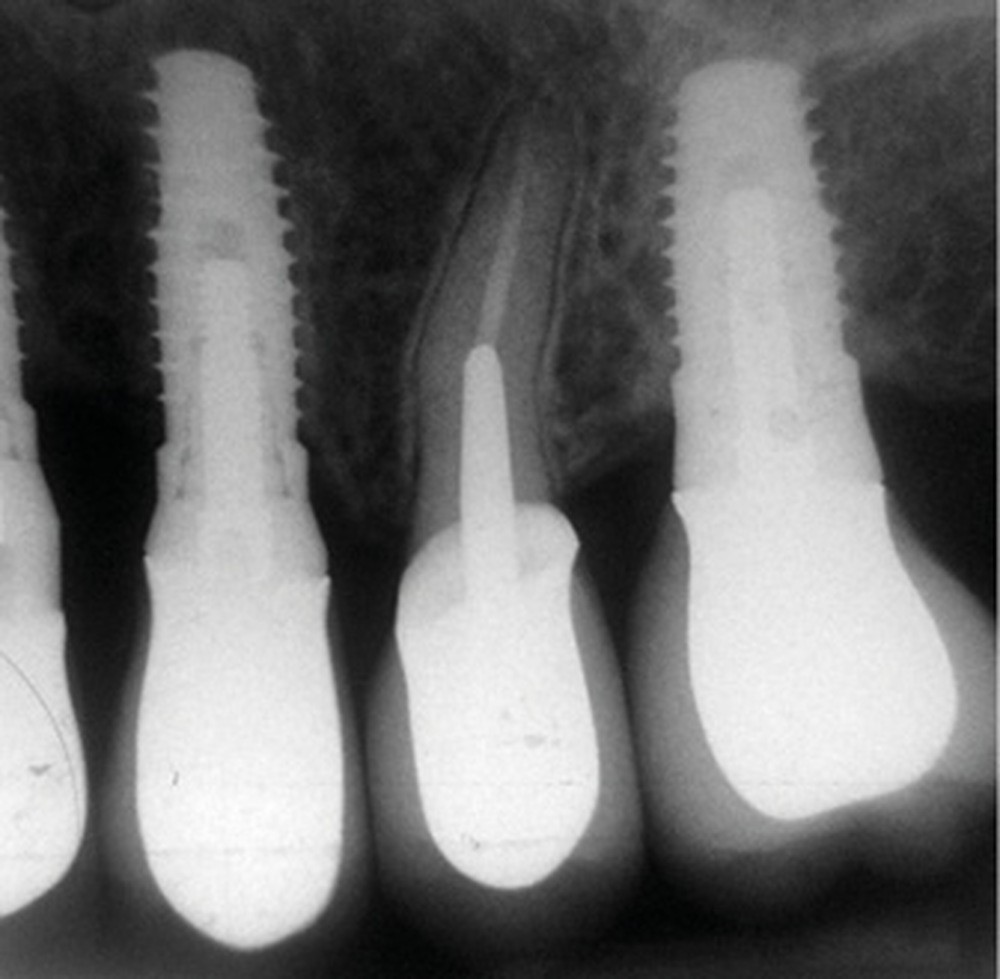

La radiographie péri-apicale au long cône confirme, sur la 25, un élargissement desmodontal, notamment en distal, des niveaux osseux mésio-distaux réduits par rapport aux clichés de contrôle précédents (les radiographies sont réalisées avec une technique parallèle avec des angulateurs de Rinn non personnalisés), un apex radiculaire normal et des niveaux osseux stables sur les implants adjacents (fig. 5). Le cisaillement systématique du fil dentaire lors de son passage confirme des points de contact très étroits entre 24, 25 et 26.